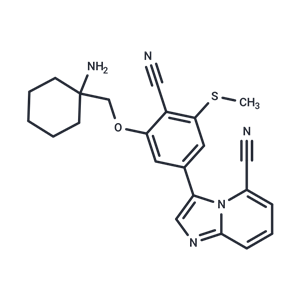

化合物 SIK-IN-4

化合物 SIK-IN-4

化合物 SIK-IN-4

SIK-IN-4

- 化合物 SIK-IN-4

- SIK-IN-4

- 3033846-10-2

- 98%HPLC